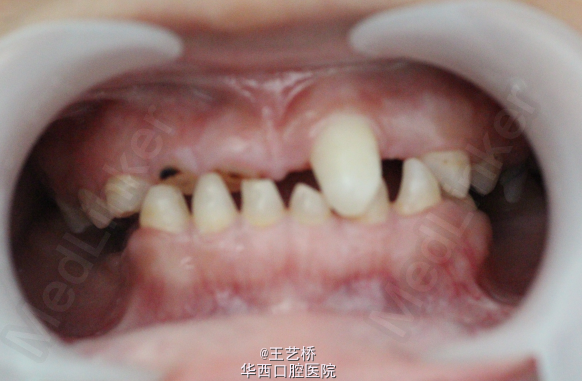

从来没有想过一个11岁的小朋友牙齿情况会是这样,在深深惋惜的同时一个巨大的问题接踵而至:我们该怎么对这个患者进行治疗呢?评估之后能够保留的牙齿我们可以进行根尖诱导或者根管治疗,但是小朋友的咬合问题应该怎么解决呢?11岁就进行修复治疗肯定是不行的,需要现在开始维持修复间隙吗?如何维持?更加亟待解决的是小朋友的咀嚼问题,能暂时使用可摘义齿恢复咀嚼吗?